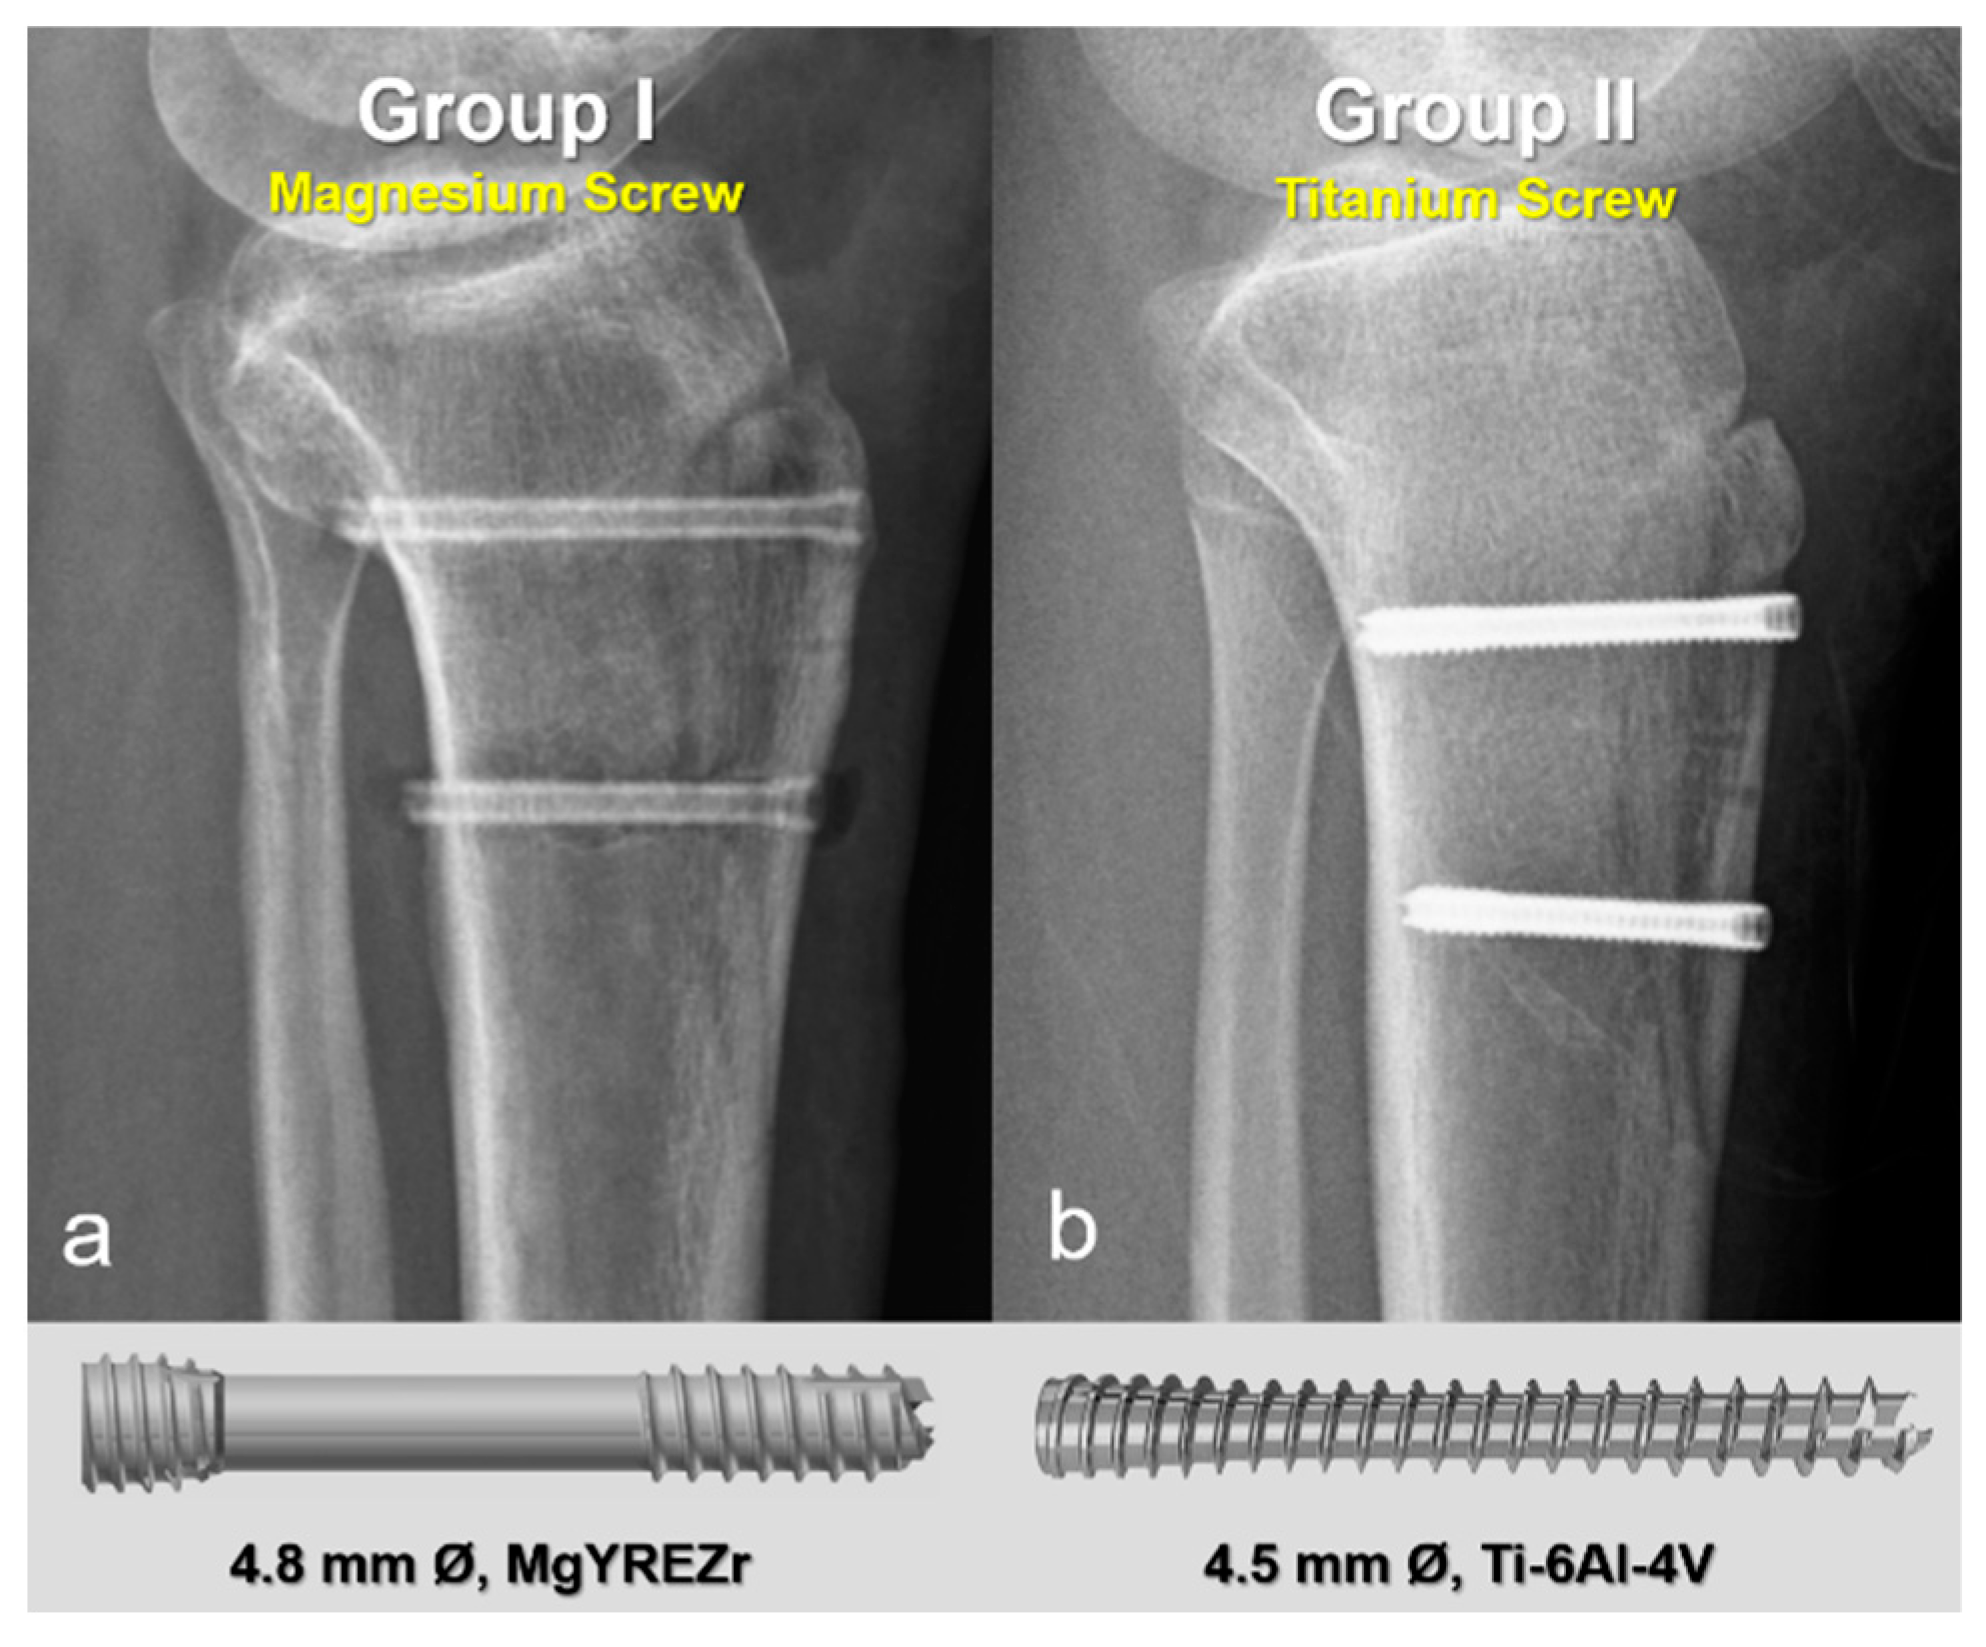

2.2. Surgical Technique and Implants

Radiographic Findings in the Mg Screw Group